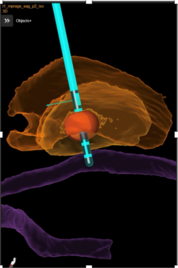

Bei bestimmten Bewegungsstörungen, die nicht oder nicht mehr ausreichend auf eine medikamentöse Therapie ansprechen, ist es möglich, die hierfür verantwortlichen Hirnareale durch die sog. Tiefe Hirnstimulation zu beeinflussen. Hierbei werden feine Elektroden in das Gehirn eingesetzt, um fehlerhafte Nervenstrukturen mit elektrischen Impulsen zu aktivieren oder zu hemmen. Beim Morbus Parkinson, dem essentiellen Tremor oder der Dystonie sind beispielsweise spezifische Hirnareale überaktiv, die dann gezielt durch die Tiefe Hirnstimulation gehemmt und die Symptome wie Zittern oder Muskelsteifigkeit dadurch unterdrückt werden können. Die Hirnregionen selbst bleiben dabei intakt, sodass die Stimulation jederzeit rückgängig gemacht werden kann. Die elektrische Stimulation wird durch einen Impulsgeber gesteuert, der ähnlich wie ein Herzschrittmacher unter die Haut an der Brust der Patient:innen implantiert wird. Die Einstellungen des Impulsgebers lassen sich von außen jederzeit verstellen, sodass die Stimulation an veränderte Bedürfnisse der Patient:innen stets angepasst werden kann.

Motorkortexstimulation

Bei bestimmten Gesichtsschmerzen und Schmerzen nach Schlaganfällen kann durch das Einbringen von einer oder mehrerer Elektroden oberhalb der Gehirnoberfläche, die für die Bewegung des Körpers verantwortlich ist, eine Schmerzlinderung erreicht werden. Die Elektoden werden entweder auf oder unter die Nervenhaut gelegt. Das Gehirn selbst bleibt intakt, sodass die Stimulation auch wieder rückgängig gemacht werden kann.

Auch bei diesem Verfahren werden die Elektroden durch einen Impulsgeber angesteuert, der unter die Haut implantiert wird. Die abgegebenen elektrischen Impulse verändern die Schmerzwahrnehmung so, dass die Schmerzen weniger stark wahrgenommen werden. Die Einstellungen des Impulsgebers lassen sich von außen jederzeit verstellen, sodass die Stimulation an veränderte Bedürfnisse der Patient:innen stets angepasst werden kann.